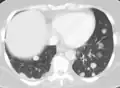

CT image of a lung metastasis -